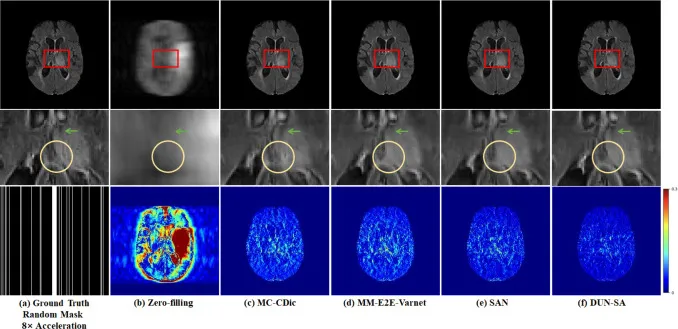

图7. 在BraTs 2018数据集上,1D随机欠采样掩模下8倍加速的代表性方法视觉比较。第一行:不同方法重建的图像;第二行:感兴趣区域的放大视图;第三行:8倍加速的随机掩模和不同方法的误差图。